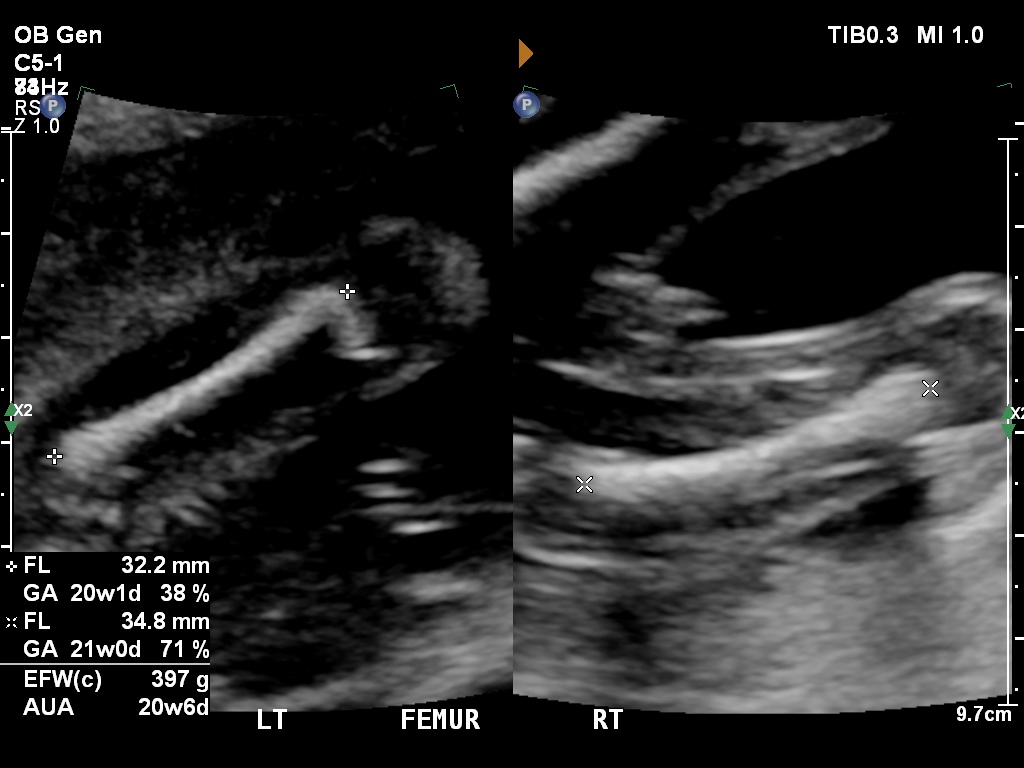

Hi there! This is a recent scan of my 20 week old baby and of the left and right femur bones (thigh bones) the picture is divided into 2, showing left and right bones. The picture on the right has the right femur and part of the left femur showing both legs apart. Are the bits in between the leg bones girl or boy parts? I love speculation!Attachment 31493Attachment 31493